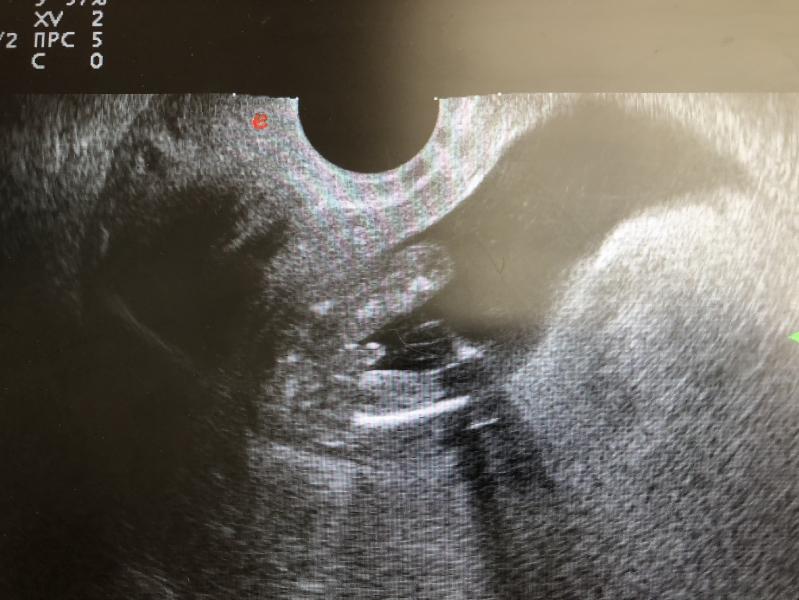

Это точно мальчик ? Или есть шанс на девочку с рукой между ног?😁😁😁

Вот я тут тоже вижу что есть достоинство))) просто с дочкой у меня вообще не было таких снимков)) вид снизу так сказать 😂😂😂😂😂

Мне кажется похоже на половые нубы.

У пацанов прям клугдые бубенцы висят

@dashalol, ой я в этом совсем не шарю, но по запросу в гугле выдало много подобных снимков как мой, и там пишут что мальчик 🤷🏻♀️😁

Сами маленькие,а уж писюли то откуда такие))))мальчик,да))

У нас так же видно яички и писюньку, мальчишка)))